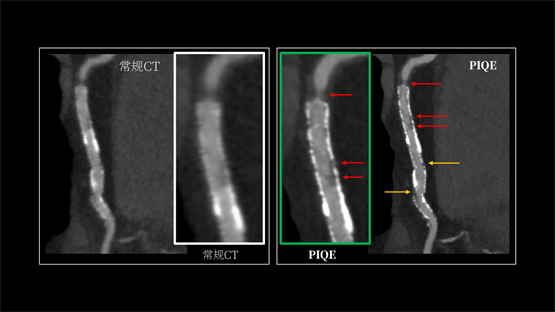

INSIGHT Pioneer利用PIQE技術(shù),首次實(shí)現(xiàn)了“16cm寬覆蓋 +超高分辨率”在同一CT系統(tǒng)上兼得。它能顯著銳化支架輪廓,有效抑制金屬偽影與硬化偽影。即便在多枚支架重疊、支架內(nèi)徑細(xì)小、嚴(yán)重鈣化或心率波動(dòng)的復(fù)雜病例中,依然能清晰顯示支架內(nèi)腔通暢情況及貼壁斑塊性質(zhì)。這意味著,醫(yī)生在手術(shù)規(guī)劃、介入治療和術(shù)后隨訪中,都能更可靠地依賴CT來確認(rèn)結(jié)構(gòu)變化。日本仙臺(tái)厚生醫(yī)院心血管內(nèi)科主任醫(yī)師Shitaro Honda在實(shí)際應(yīng)用中反饋:“PIQE使直徑2.25mm的細(xì)小支架也能清晰呈現(xiàn),能更清晰地顯示血管。”

(左圖為常規(guī)圖像,右圖為應(yīng)用PIQE技術(shù)后的超高清圖像)